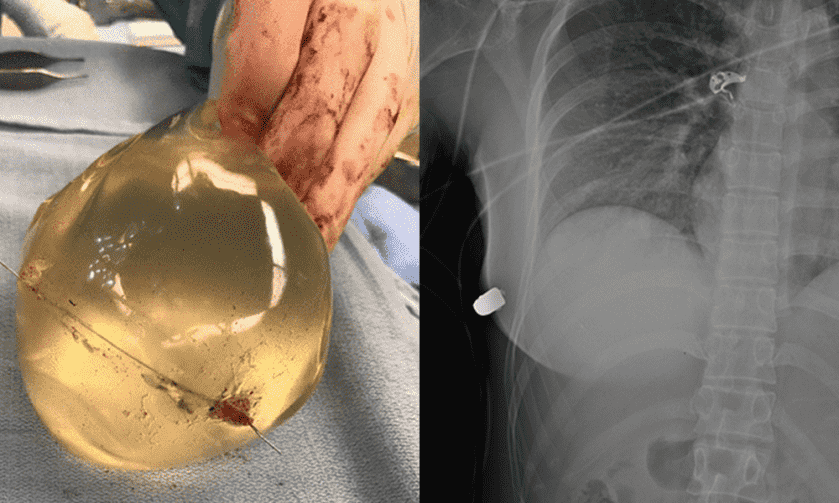

The copper-jacketed .40-caliber projectile entered the woman’s left breast, but doctors discovered the bullet lodged in the lower portion of the right breast. The woman suffered a broken rib, broken implants, and a gunshot wound but was otherwise unscathed.

“The bullet entered the skin on the left side first, and then ricocheted across her sternum into the right breast and broke her rib on the right side,” surgeon Giancarlo McEvenue told CNN. “The implant caused the change in the trajectory of the bullet.”

“Based on trajectory of bullet entry clinically and evaluation radiologically, the only source of bullet deflection of the bullet is the left breast implant. This implant overlies the heart and intrathoracic cavity and therefore likely saved the women’s life,” the report concludes.